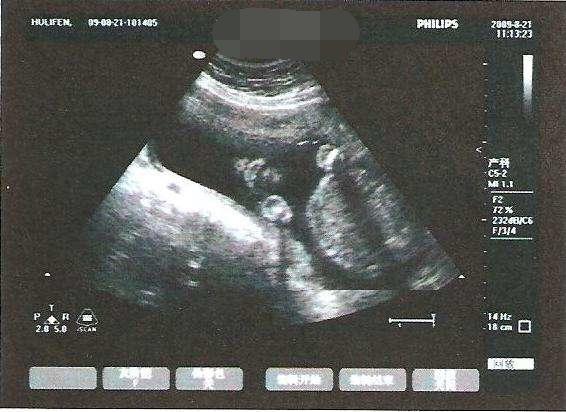

说起“绑绳”这个词语,可能很多人并不能够真正理解,其实也就是我们常说的“脐带绕颈”,当然也包括“绕足”、“绕腿”等情况。这些问题一旦出现,就会对胎儿产生极大的威胁。因为胎儿在子宫里,是通过脐带和外界取得联系。他们通过脐带获取生存必须的氧气、水分以及各种营养物质,因此可以说脐带就是他们生命的“按钮”。如果发生脐带绕颈等现象,胎儿的生命通道被阻断,随时会面临着生命危险。

脐带其实属于一个中介物质,完美地将婴儿的肚脐和子宫内壁连接起来,剩下的部分就会漂浮在羊水之中。如果胎儿成长缓慢、本身体积过小,脐带就很有可能缠绕到孩子,并且很难自动解开。随着时间的推移,婴儿在逐渐长大,脐带就会越缠越紧,导致胎儿出现严重缺氧。这种情况是很危险的,需要第一时间去医院求助专业医护人员的帮助。稍有不慎,就可能会要了胎儿的性命。